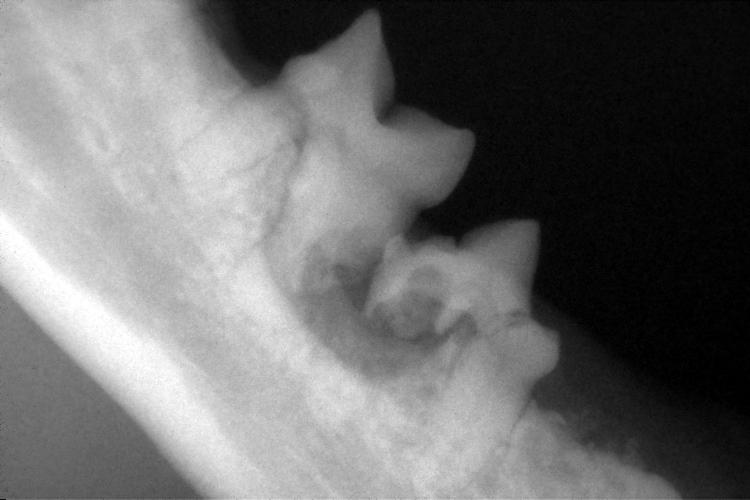

歯科レントゲン

右下顎臼歯のレントゲンです。

破歯細胞性吸収病巣により、歯根の一部が溶けていることが確認できます。(黄色斜線部分)

左下顎第1後臼歯も破歯細胞性吸収病巣により歯冠と歯根の一部が溶けていました。(歯色斜線部分)